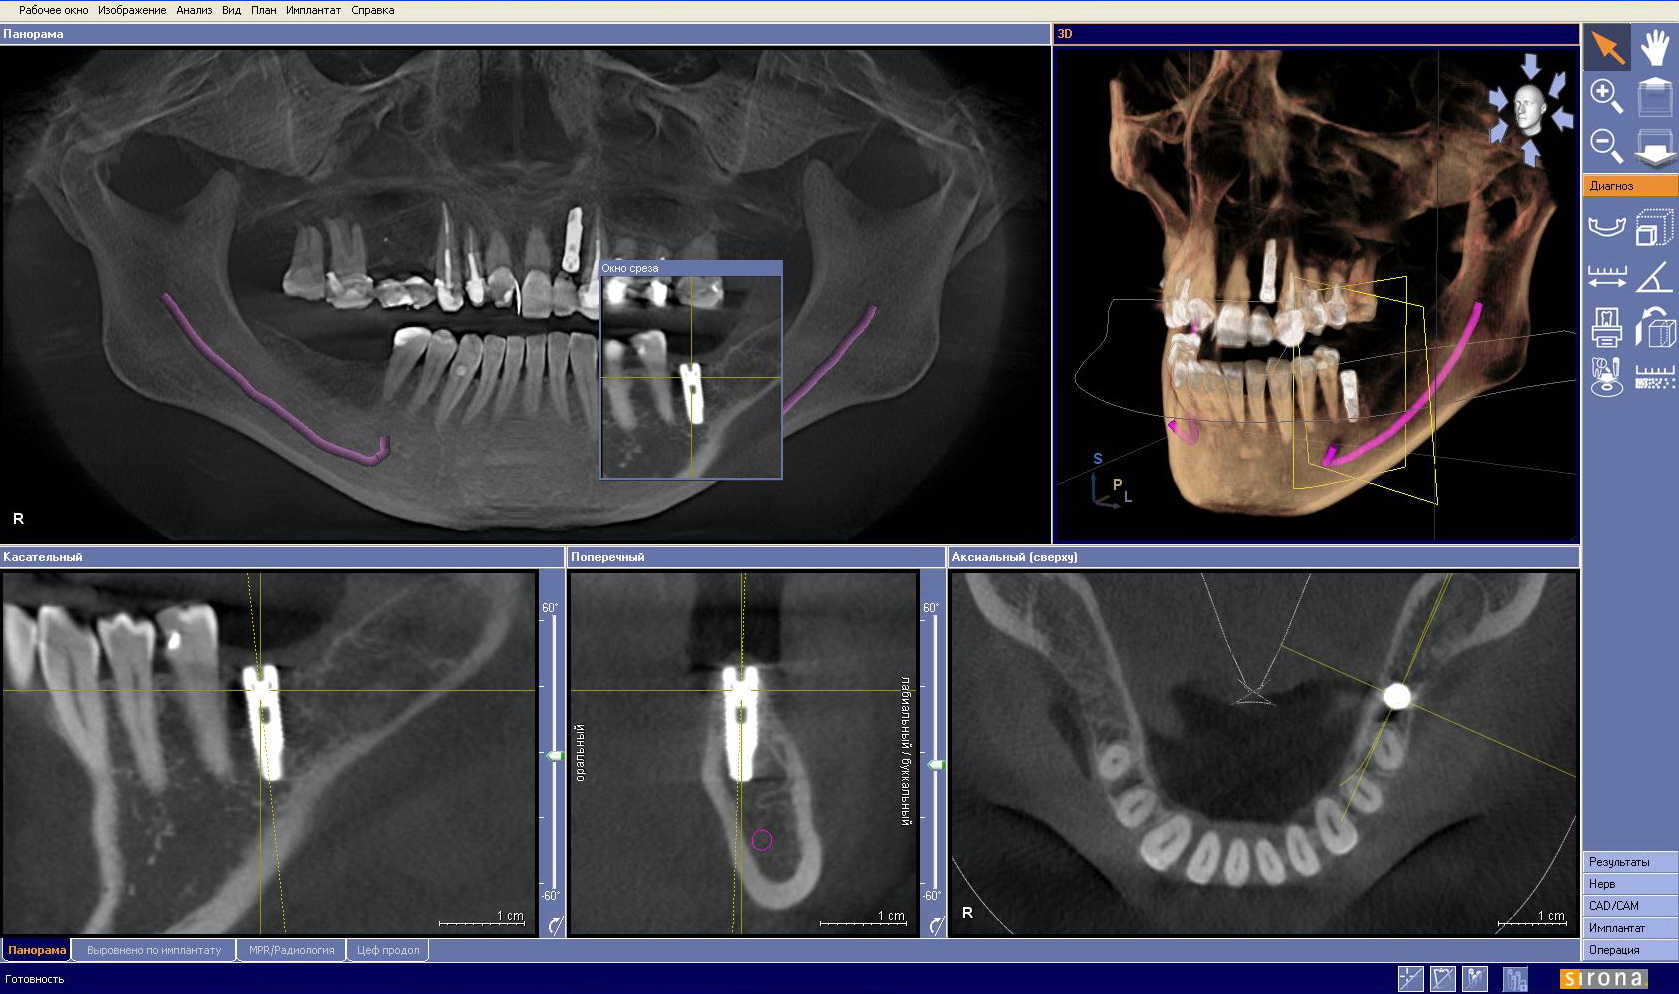

Ранее для изучения состояния зубной полости использовались рентгеновские снимки, показывающие лишь плоские изображения. Компьютерная томография (КТ) — усовершенствованный вариант рентгена, предоставляющий трехмерные изображения. Это позволяет стоматологу видеть не просто плоские снимки, а полноценную трехмерную модель челюсти пациента с учетом всех патологий. Такой подход дает возможность детально изучить челюсть, рассматривая ее по слоям и точно определяя глубину проблемы.

Кроме того, 3D томография помогает стоматологам в планировании имплантации, позволяя точно оценить состояние костной ткани и выбрать подходящее место для установки импланта. Она также используется для оценки результатов лечения и мониторинга динамики заболеваний. Внедрение этой технологии способствует улучшению качества стоматологической помощи и снижению рисков осложнений.

Как выглядит снимок?

Компьютерная 3D томография зубов становится все более популярной среди стоматологов и пациентов. Эта процедура позволяет получать качественные изображения зубочелюстной системы, что облегчает диагностику. Пациенты отмечают, что 3D томография помогает врачам точнее разрабатывать планы лечения, особенно в сложных случаях, таких как имплантация и ортодонтия.

Процедура также выявляет скрытые проблемы, например, кисты или опухоли, которые могут не быть видны на обычных рентгеновских снимках. Многие пациенты чувствуют себя увереннее, зная, что их стоматолог имеет полное представление о состоянии их здоровья. В целом, отзывы о процедуре положительные, и пациенты ценят ее информативность и безопасность.

- получаемый 3D снимок дает развернутую информацию о состоянии зубного ряда, скрытых проблемах с челюстью, ширине кости;

КТ, в свою очередь, обеспечивает многослойное сканирование, что позволяет врачу «прокладывать» путь через различные слои тканей и получать изображения с разных углов. Это особенно полезно при диагностике заболеваний, которые могут быть скрыты от глаз при использовании других методов. Например, при наличии зубного импланта КТ позволяет оценить его положение относительно соседних зубов и костной ткани, что критично для успешного результата операции.